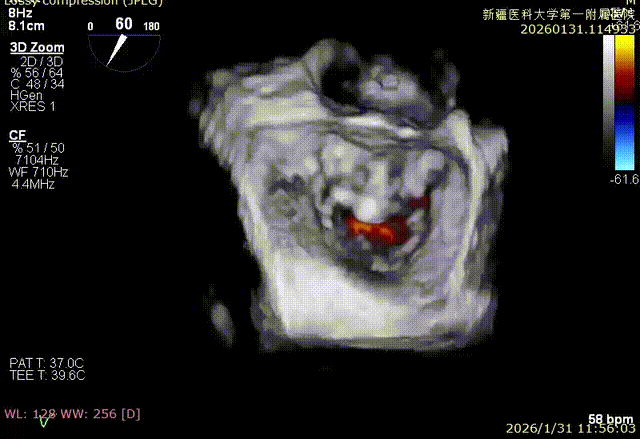

3D enface反流充分降低

该例患者为VFMR,病变位于2区,反流为中心性反流。术前制定手术策略:使用1把XTR解决患者二尖瓣反流。术中首先进行房间隔穿刺,最终穿刺高度4.2cm。穿刺成功后将SGC和XTR-CDS依次送入左心房,通过操控“M”旋钮调节SGC,使二尖瓣夹避开华法林脊并成功定位于2区正上方。在2区进行弹道测试成功后,进行Orientation调整。最终在2区将二尖瓣夹送入左心室,成功捕捞和夹持瓣叶后缓慢关紧夹臂。TEE检查见二尖瓣反流程度降低至微量,二尖瓣双孔组织桥稳定,跨瓣压差1mmHg,肺静脉逆流改善明显,手术安全结束。